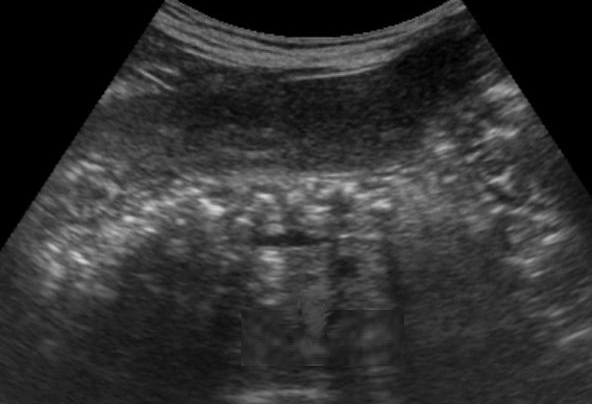

. Echographie :

Image echographique

percutanee direct de

pancreatite chronique est image de hyperechogene

heterogeneite de la

parenchyme pancreatique , sa taile peut augemente ,

normalement ou diminue sa bord est irregulier ,parfois

en presente des nodules calcification parenchymeteuse ou bien

image calcaire des calculs du canal pancreatique ce qui donne

de aspect de cone de l.ombre posterierure, en ce cas les

canal intra pancreatique sont dilates .

Les faux kyste associe peut en presente et se donne des images aechogene ou

hypoechogene intrapancreatique . Imge de ascite parfois se

en voyait